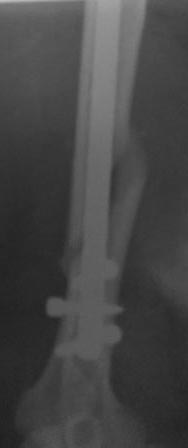

Операция 16.03.17г. БИОС закрытым способом СhM под ЭОП.В ходе рассверливания к/м канала дистального отломка, видимо, имеющийся осколок откололся , но стояние было удовлетворительное, в конце операции при контрольной проверке под ЭОП все было нормально (см.снимки под ЭОП).

На контрольной Р-грамме на следующий день – осколок сместился. Коллеги рекомендуют или щилом втолкнуть, или маленьким разрезом открыть и репонировать, и т.д.

по поводу "противных рентгенологов"))... на снимках ЭОП и R-грамм разница в проекциях градусов 30!..Ну , а если осколок так легко "гуляет",то плечо навряд ли простит такое,не?